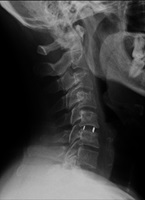

Se aprecia la prótesis de disco colocada entre C5 y C6 | ||||